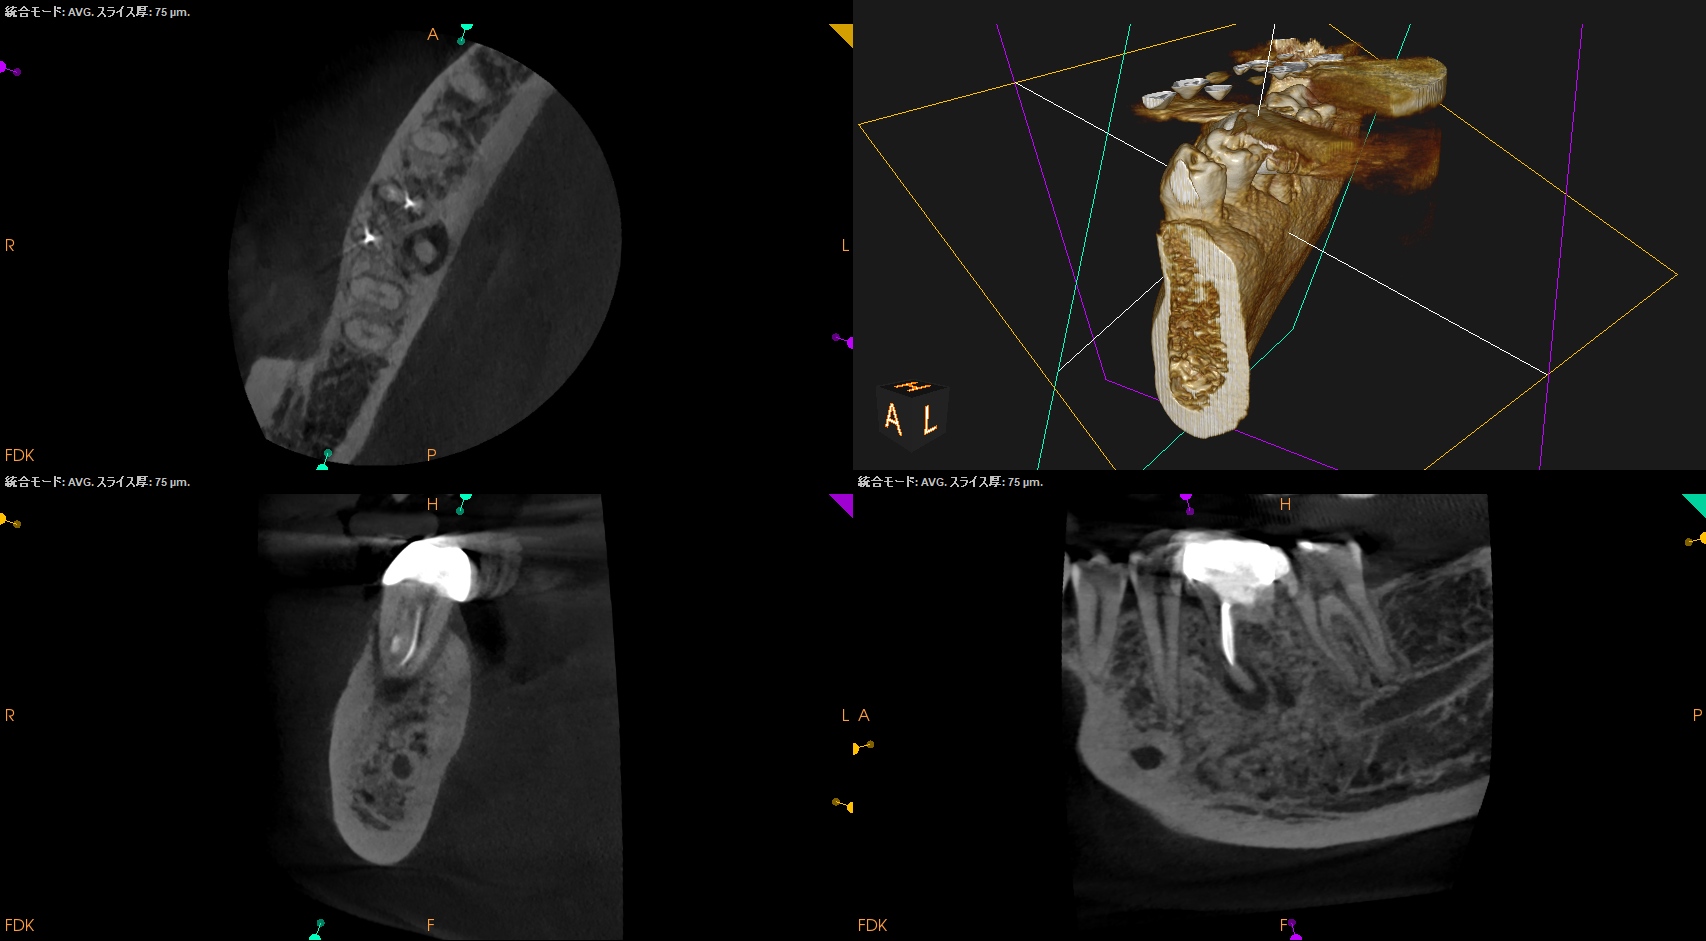

#30 Re-RCT 1yr recall(2026.3.10)

MB

ML

D

Radix

初診時と比較した。

病変は完治した。

このことから最終補綴もOKだし、経過観察も終診とさせていただいた。

長きに渡りお疲れ様でした。